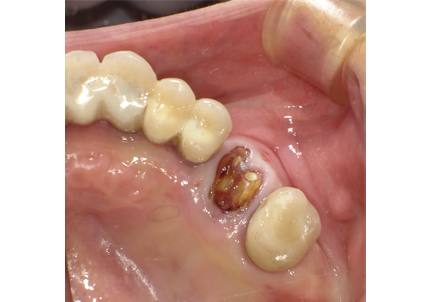

15.右下6番近心根抜歯(2016年12月12日)

↑術後1か月(2017年1月7日)